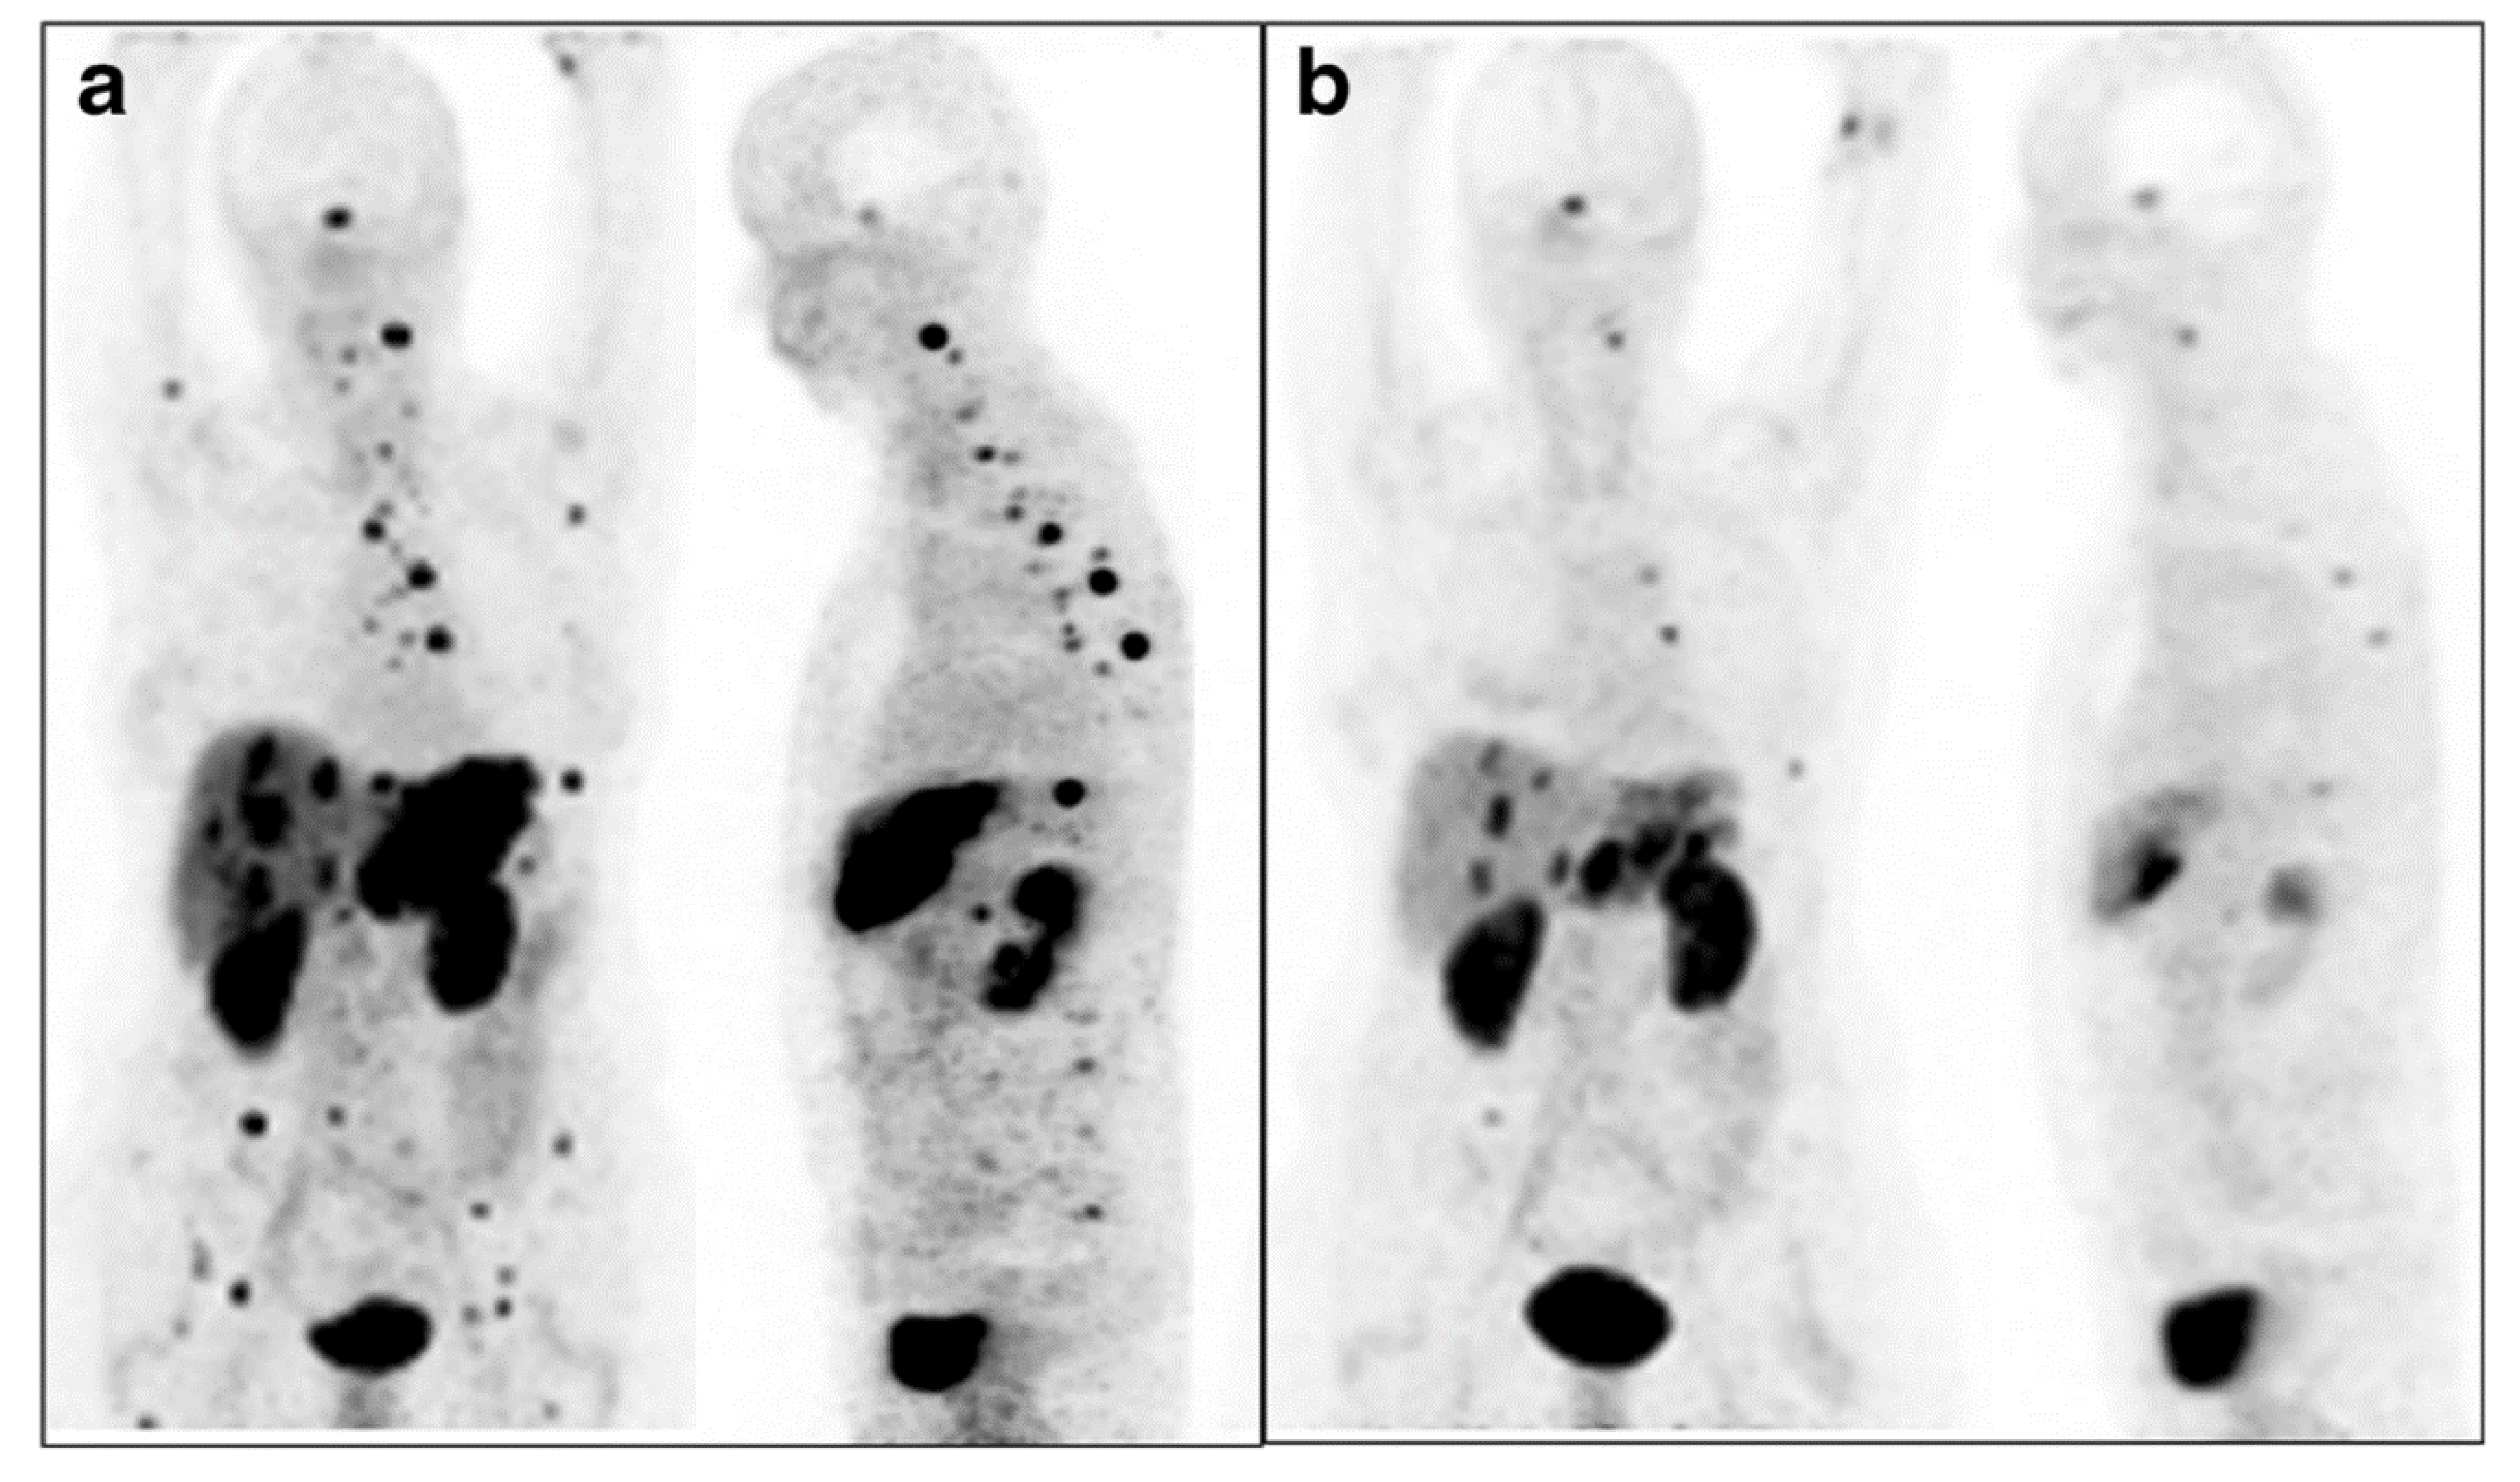

- Kratochwil, C.; Bruchertseifer, F.; Giesel, F.L.; Weis, M.; Verburg, F.A.; Mottaghy, F.; Kopka, K.; Apostolidis, C.; Haberkorn, U.; Morgenstern, A. 225Ac-PSMA-617 for PSMA-targeted α-radiation therapy of metastatic castration-resistant prostate cancer. J. Nucl. Med. 2016, 57, 1941–1944. [Google Scholar] [CrossRef]

- Kratochwil, C.; Haberkorn, U.; Giesel, F.L. 225Ac-PSMA-617 for Therapy of Prostate Cancer. Semin. Nucl. Med. 2020, 50, 133–140. [Google Scholar] [CrossRef]

- Sathekge, M.; Bruchertseifer, F.; Knoesen, O.; Reyneke, F.; Lawal, I.; Lengana, T.; Davis, C.; Mahapane, J.; Corbett, C.; Vorster, M. 225Ac-PSMA-617 in chemotherapy-naive patients with advanced prostate cancer: A pilot study. Eur. J. Nucl. Med. Mol. Imaging. 2019, 46, 129–138. [Google Scholar] [CrossRef]